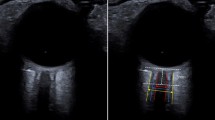

The deformability index (DI) is a novel dynamic optic nerve sheath parameter. It describes the relative lateral motion of opposite sides of the optic nerve sheath occurring with each cardiac cycle and hypothesizes that this relative motion is nonsymmetrical in states of low ICP and becomes more symmetrical in states of high ICP (Fig. 1). DI can be obtained by processing of ultrasound videos of the optic nerve sheath and can, like ONSD, potentially be available at the bedside.

Illustrative figure of the optic nerve sheath complex (middle) with ultrasound images depicting ONSD (left) and DI (right). Red dots are placed on the optic nerve sheath in both the illustrative figure and the ultrasound images. ONSD is the distance between the two opposite points on the optic nerve sheath 3 mm posterior to the retina measured on a still image. DI is a dynamic parameter based on the same two points on the optic nerve sheath but uses automatic speckle tracking to identify the lateral movement of these points on ultrasound videos. DI estimates the magnitude of motion in the lateral direction on both sides of the nerve sheath complex (D1 and D2) over the cardiac cycle and quantifies the deformation of the nerve sheath according to the formula DI = (D1 − D2) / (D1 + D2). The proposed concept hypothesizes that the lateral movement of D1 and D2 is asymmetrical when ICP is low and becomes more symmetrical when ICP is high. CSF cerebrospinal fluid, DI deformability index, ICP intracranial pressure, ONSD optic nerve sheath diameter (Color figure online)

Deformability Index

DI was calculated according to the method previously described by our research group [4, 5]. It estimates the magnitude of motion in the lateral direction on both sides of the optic nerve sheath (D1 and D2) over the cardiac cycle (Fig. 1) and quantifies the deformation of the nerve sheath complex according to the formula DI = (D1 − D2) / (D1 + D2). In this study, manual initialization of two opposite points on the optic nerve sheath was used before automatic speckle tracking of the lateral motion of the points was performed. The depth of initialization was standardized at 3 mm from the sclera. To reduce variability from the manual initialization, DI was processed three times, and resultant values were averaged for each eye. Averaged values between the two eyes were used for final analysis.

Secondly, DI was calculated by semiautomated postprocessing of ultrasound videos in the present study, whereas the method’s intended use is as a bedside parameter. This reflects the method’s stage of development during the inclusion phase of this study. In our study, two opposite points on the optic nerve sheath were manually initialized before automated speckle tracking of the motion of the points was performed. Ultimately, automatic identification of the opposite points on the optic nerve can make the method fully automated and hence make DI calculations available at the bedside at the time of measurement. These opposite points on the optic nerve sheath relate to the points between which ONSD is measured (Fig. 1). Indeed, the software for automatic identification of these points using real-time segmentation of the optic nerve sheath complex using machine learning has been developed and was tested on its ability to perform automated measurements of ONSD in a recently published study [20].